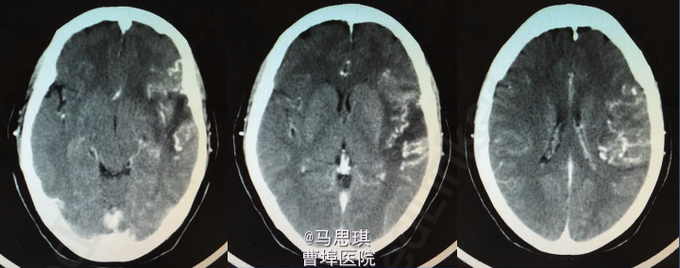

入院诊断为:“脑梗塞?” 患者有溶栓指征,但患者家属拒绝溶栓。 治疗: 氯吡格雷75mg Qd 拜阿司匹林0.1 Qd 立普妥 20mg qd 胞磷胆碱0.2tid 依达拉奉30mg ivgtt bid 康复治疗 入院第二天行MRI及MRA检查。 头部MRI:左侧额颞岛叶见片状稍长T2稍长T1信号灶,其内见较多增粗、增多血管影,原因?考虑:血管畸形所致左侧额颞岛叶缺血梗塞性改变?血管炎性病变或脑炎待排? 头颅MRA:左侧额颞岛叶见较多增粗、增多的血管影,右侧额颞顶交界区血管影稍增多。左侧胚胎型大脑后动脉。 入院第四天行头颅增强CT及CTA。 头颅增强CT:左侧颞叶见片状低密度影,其内见大小约0.7x1.6cm片状高密度影,与前片比较,见范围加大,考虑系梗塞后伴出血,血管畸形。增强扫描见左侧额颞叶较多迂曲扩张的血管影。 CTA:左侧额颞岛叶区域见大脑中动脉岛叶段,侧裂段及分叉段分支明显增多,部分迂曲、扩张,呈杂乱走行的血管团样改变,考虑血管畸形可能;右侧额顶交界区血管影稍增多。双侧颈内和基底动脉及大脑前中后动脉显示清晰,其大小、走行、信号未见确切异常,各血管壁光整,管腔未见确切狭窄,走行自然。 发现出血后,停用双联抗小板治疗,并加做DSA DSA示:左侧颈外动脉分支脑膜中动脉血管畸形,与颈内动脉,椎动脉无明显交通 修正诊断为: 左侧额颞岛叶脑梗塞并梗塞后出血; 左侧脑膜中动脉血管畸形 动脉粥样硬化症 上呼吸道感染